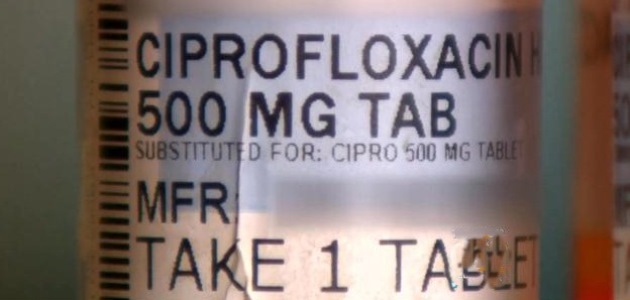

The agency has enhanced the warnings about these antibiotics’ association with disabling and potentially permanent side effects and to limit their use in patients with less serious bacterial infections. FDA says fluoroquinolones should be used for some conditions only when there are no other options available.